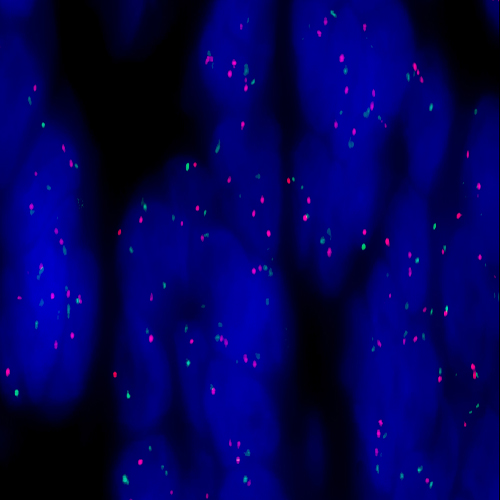

Human tonsil: immunohistochemical staining for CD22. Note the mantle zone is staining stronger than the germinal centre. CD22: clone FPC1

L'antigène CD22 (BL-CAM) est une glycoprotéine membranaire intégrale de type 1 d'un poids moléculaire de 130 à 140 kD. C'est un hétérodimère de deux chaînes glycoprotéiques exprimées indépendamment, présent sur la membrane et dans le cytoplasme des lymphocytes B.

L'expression de l'antigène CD22 commence tôt dans la différenciation des lymphocytes B, approximativement au même stade que l'expression de l'antigène CD19. L'expression de l'antigène de surface est variable et peut être perdue après différenciation.

On a aussi détecté une faible expression de l'antigène CD22 dans les leucémies myéloïdes et dans les leucémies lymphoïdes aigües à cellules non-T, et une expression forte dans les leucémies à cellules chevelues. Il est absent des lymphocytes T du sang périphérique, des leucémies à cellules T, des granulocytes et des monocytes.